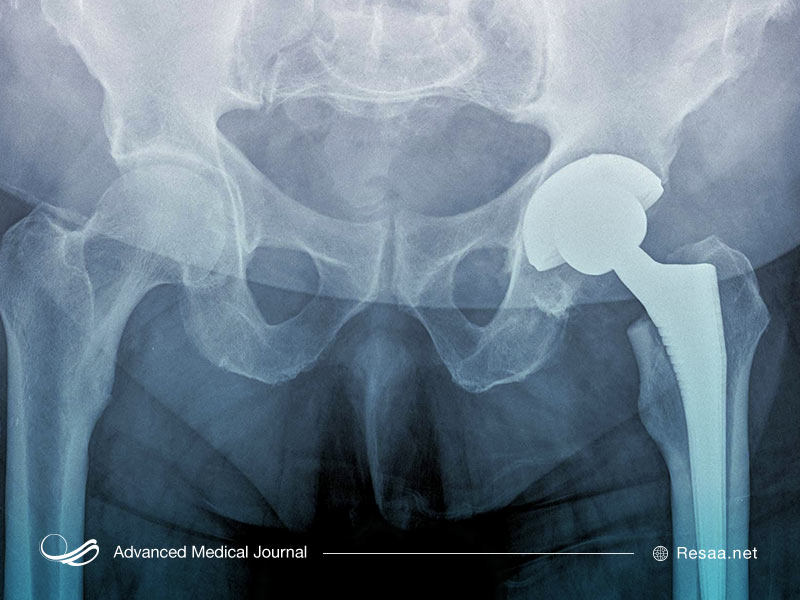

استئولیز Periprosthetic

نوع دوم استئولیز میتواند به عنوان عوارض جراحی تعویض مفصل ایجاد شود. بیشتر بیماران پس از جراحی تعویض مفصل بدون هیچ عارضهای بهبود مییابند. اما گاهی اوقات پلی اتیلن یا سایر مواد موجود در کاشت مفصل ممکن است از بین بروند. وقتی این اتفاق میافتد، بقایای موجود در بافت مفصلی اطراف آن جمع میشود. این وضعیت به نوبه خود باعث التهاب میشود و میتواند منجر به تحلیل رفتن استخوان گردد.

در افرادی که تعویض مفصل در آنها باعث جایگزین مفصل ران و زانو یا مفصل دیگر شده است، علامت اصلی استئولیز periprosthetic شل شدن آسپتیک پروتز مفصل است (یعنی شل شدن ایمپلنت بدون هیچ گونه نشانهای از عفونت).

اغلب این وضعیت تا دیرهنگام و پس از از دست دادن گسترده استخوان، هیچ علامتی ایجاد نمیکند. به همین دلیل، بیماران تعویض مفصل باید به طور دورهای درمان اشعه ایکس مفصل خود را پیگیری کنند.

اگر جایگزین مفصلی انجام دادهاید و بعد از مدتی علائم فوق را تجربه کردهاید، جراح میتواند ابتدا آزمایشات، عکس برداری با اشعه ایکس و تصویربرداری MRI را انجام دهد تا ببیند آیا شما عفونت پس از جراحی دارید که از استئولیز پروپروتز جدا باشد.

این اختلال اگر زود تشخیص داده شود، این احتمال وجود دارد که از درمانهای مختلفی برای درمان التهاب و جلوگیری از استئولیز بیشتر استفاده شود. اگر از دست رفتن استخوان گسترده تشخیص داده شود، ممکن است درمان به منظور اصلاح مفصل به جراحی نیاز داشته باشد (به عنوان مثال انجام اصلاحات در مفصل ران یا اصلاح در زانو).